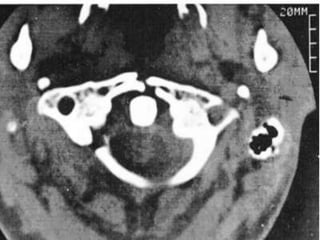

FRATURAS DO ATLAS

 A estabilidade dessas fraturas está relacionada com

a integridade do ligamento transverso

 Critério de Spence:

 Análise da radiografia transoral do paciente antes

do tratamento:

 Fratura instável : quando o afastamento das massas

laterais do atlas em relação ao áxis for maior do

que 6,9mm

 IAO: até 5 mm somente lig transvero; > 5mm tb

dos lig alates

 TC para melhor avaliação